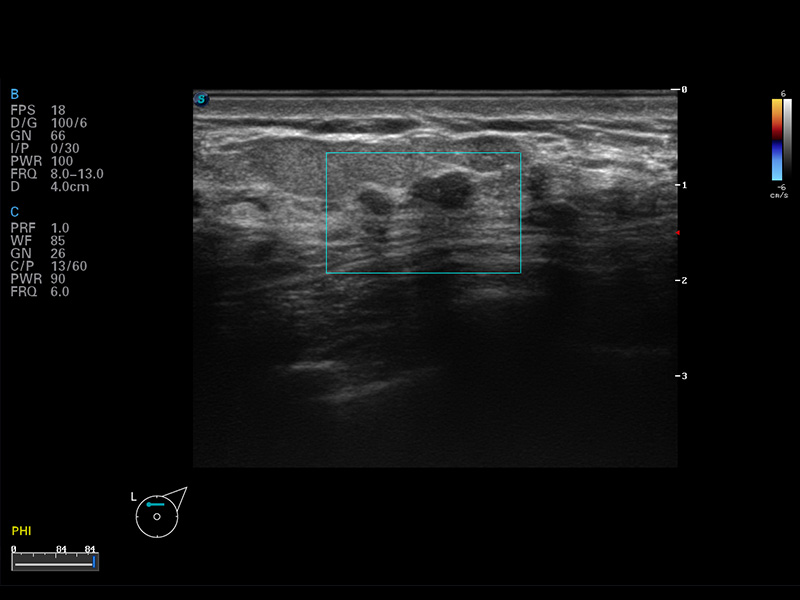

乳腺结节